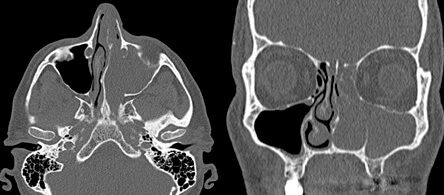

В диагностике инвертированных папиллом ключевое место занимают лучевые методы исследований

- компьютерная томографии

- магнитно-резонансная томографии (с контрастом по назначению врача).

Ценность КТ – материалов состоит в возможности точной оценки границ опухоли, что позволяет определить стадию процесса и тактику дальнейшего ведения больного. МР-данные позволяют дифференцировать активный воспалительный процесс в пазухах от фиброзной и рубцово-измененной ткани. Введение контрастного препарата повышает яркость свечения воспаленной слизистой оболочки.